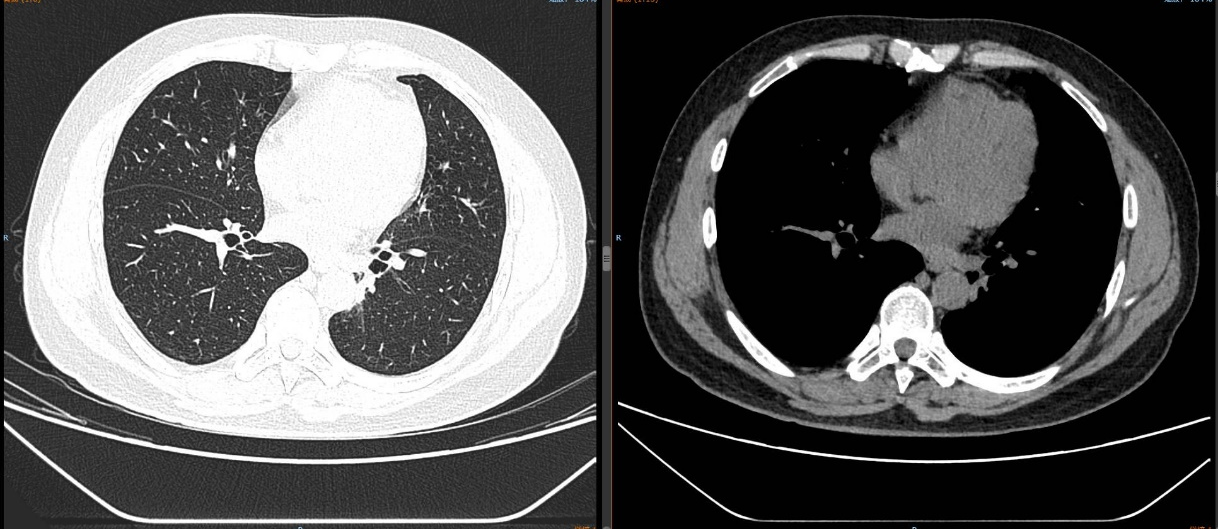

现病史:2024-11-18外院体检时行胸部增强CT示:两肺纹理增多,左肺下叶软组织密度影,大小约3.7*3.1cm,边缘见少许毛刺影,周围见少许斑片模糊影,左肺见多发结节影,最大径约9mm。左肺下叶占位,考虑肺癌,请结合纤维支气管镜及生化检查。左肺多发结节,肺内转移不排除。

2024-11-26 胸部CT检查示:

2024-11-26 PET-CT进一步评估:左肺下叶背段近肺门处类圆形分叶状肿块(约32*28mm),FDG代谢异常增高;纵隔内4L组、左下肺门处、左侧膈肌脚内侧见稍大淋巴结FDG代谢增高,左肺内及胸膜下散在多发结节影,FDG代谢不同程度增高,考虑左肺下叶肺癌伴左肺及胸膜多发转移、多发淋巴结转移。